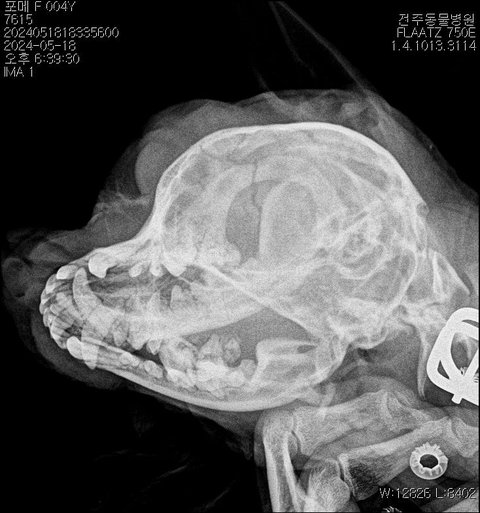

구례학대 포메 공주를아시나요?

✅️보호소에서 입양되어 그리고또 구례부모님집에

버려져 밖에묶여살다 이웃집남자의 폭행으로

두개골파손 뇌손상때문에 시력상실 척추마비등

1차병원에서 안락사권유한 포메 공주의이야기입니다

공주는 구례에서 전주1차병원 그리고

전주에서 안산종합병원까지 죽을고비를

넘기며 치료를하고 있어요.